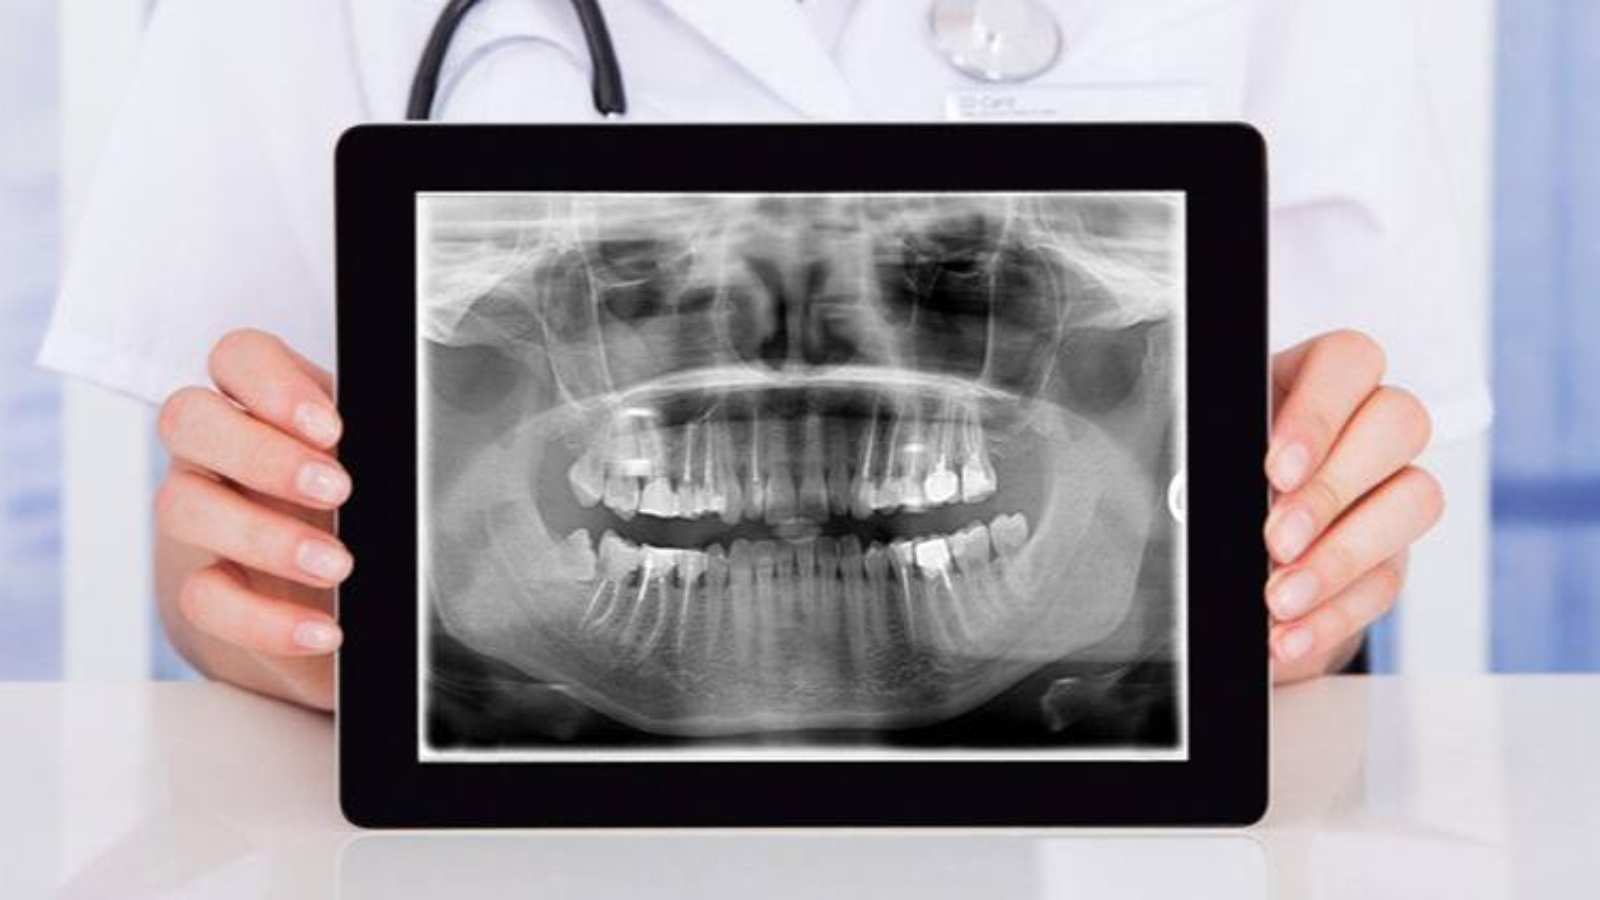

Modern dentistry requires not only precision in individual procedures, but also the ability to perceive the clinical situation as a whole rather than in isolated fragments. In the clinical philosophy of Professor Alexander von Breuer, the diagnostic stage is regarded as the foundation of any well-reasoned intervention, where every decision must be based on objective data rather than assumptions. At DentalClinic24, this approach is implemented through the use of orthopantomography as a tool that provides a comprehensive view of the dentofacial system and allows treatment to be planned on the basis of systemic analysis rather than isolated symptoms.

Panoramic imaging enables the clinician to simultaneously assess tooth positioning, root condition, bone structure, temporomandibular joints, and anatomical features that cannot be fully evaluated through localized examination. This approach is especially important in cases where the clinical picture is formed by a combination of factors rather than a single isolated issue. Within the clinical approach of DentalClinic24, orthopantomography is not used routinely, but rather as a targeted diagnostic tool that forms a complete clinical model on which the entire treatment strategy is built.

A key advantage of panoramic diagnostics lies in its ability to detect hidden processes that may not present clinically at early stages. These may include chronic inflammatory lesions, impacted teeth, changes in bone structure, or developmental features of the dentofacial system. Without such information, the clinician’s decision-making becomes inherently limited, which may compromise treatment accuracy. Within the clinic’s practice, panoramic imaging allows potential risks to be identified in advance and incorporated into the treatment plan.

The clinical value of orthopantomography becomes particularly evident in complex cases requiring multidisciplinary collaboration. Orthodontic treatment, implant placement, surgical interventions, and full dental rehabilitation demand a coordinated approach and a shared understanding of the clinical situation. A panoramic image serves as a common reference point for specialists, allowing treatment strategies to be aligned and inconsistencies to be avoided. At DentalClinic24, such coordination is considered a standard component of high-quality care.